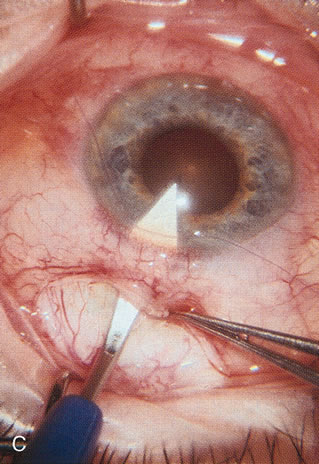

In years past, patients with both cataract and glaucoma frequently provided overwhelming surgical challenges for the ophthalmologist. The ability to carry out phacoemulsification through a 3.2-mm corneal incision along with inserting a foldable IOL is a vast improvement over 11-mm incisions that were common a decade ago (Fig. 1). The anatomical and inflammatory changes to the eye are less with small incision techniques, improving the likelihood of success with concomitant glaucoma surgery. Pharmacologic inhibition of fibrosis along with postoperative wound revision increases the long-term success rate of filtration surgery when combined with lens extraction. (Fig. 2). The learning curve may be steep at times, but the blending of cataract and glaucoma surgical skills slowly falls into place as the surgeon constantly learns and upgrades his or her technique.

Fig. 1. The anatomic advantage of small incision cataract surgery for the glaucoma patient. A. Long-term bleb function with a large cataract incision is difficult to achieve with either ECCE-trabeculectomy or trabeculectomy followed later by ECCE. This bleb failed to form sufficiently when combined with large incision ECCE. The inflammation, bleeding, and long-term wound healing with stimulation of fibroblasts associated with this technique are more likely to cause bleb failure. In addition, the increased iris manipulation necessary to deliver the nucleus and subsequent iris repair adds to the long-term breakdown of the blood aqueous barrier. B and C. Two-site phacotrabeculectomy has the advantage of small incision cataract surgery combined with separate site trabeculectomy. The incision size is one third the size of the standard ECCE. The inflammation is less severe, and cataract wound healing is confined to the temporal area. Visual rehabilitation with phacoemulsification and foldable IOL is much faster. Phacoemulsification allows successful lens extraction even in the unfriendly environment of a smaller pupil compared with ECCE. The trabeculectomy is performed in an entirely different site, well away from the wound healing associated with temporal phacoemulsification. The likelihood of this filter functioning long-term is greater than with ECCE-trabeculectomy. D. The surgeon also has the option of single-site phacotrabeculectomy with foldable IOL. Both the lens extraction and trabeculectomy are performed through one small 3.5-mm limbal incision.